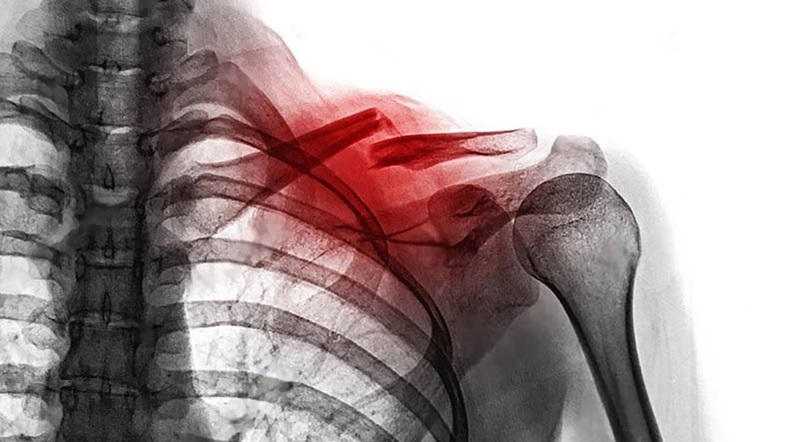

Gãy xương quai xanh thường xảy ra do các tác động lực mạnh vào vùng vai hoặc ngực. Một số nguyên nhân phổ biến bao gồm:

Thông thường, gãy xương quai xanh không trực tiếp đe dọa tính mạng, nhưng nếu không được điều trị đúng cách, nó có thể gây ra các biến chứng nghiêm trọng như:

- Tổn thương dây thần kinh và mạch máu

- Lệch xương, mất chức năng vai

- Chậm liền xương hoặc không liền xương